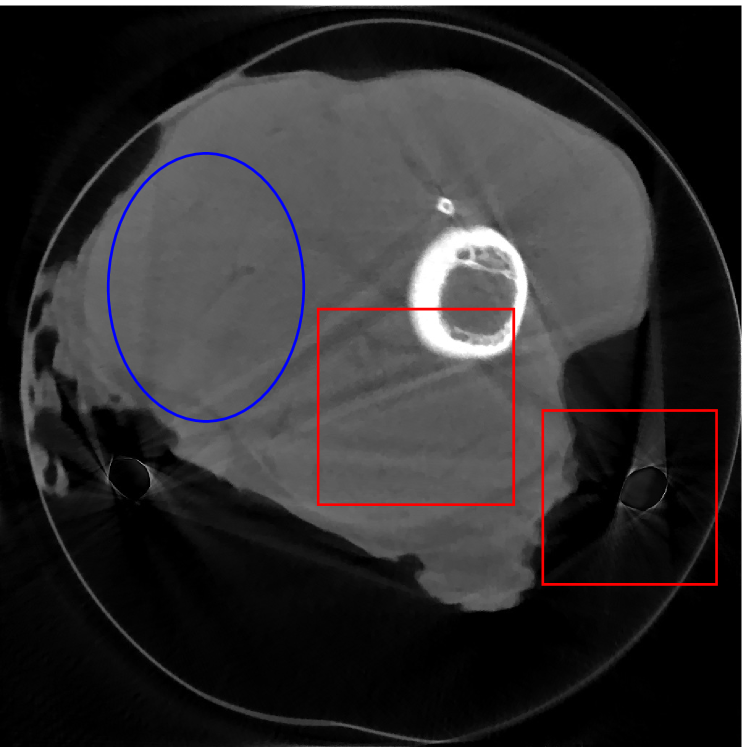

4.2 Numerical experiments: real data

We perform a CT scan of a chicken leg placed in a disposable cup (Figure 10(a)). We first scan the chicken leg without metals (Figure 10(b)) to create a reference image using FBP algorithm. Then, we place two steel thread nails on each side of the chicken leg and scan the subject again using the same scanning protocol (Figure 10(c)). The projection data is acquired from a MicroCT scanner equipped at the Division of Nuclear Technology and Applications, Institute of High Energy Physics, Chinese Academy of Sciences. The X-ray source is with 90 kV and 70 mA energy and the flat plane detector contains pixels. The scanning trajectory is a full circle with equally spaced views at per view. The physical size of each detector unit is . The distance from the X-ray source to the detector is . In order to conduct a 2D experiment, we choose the 512th row of the detector array.

Figure 11 shows the images reconstructed using FBP, the analysis model (2.12), the inpainting model (2.13) and the segmented image from the image obtained by (2.14). The reference image without metal implants are shown in Figure 11(a). All the images in this subsection are displayed within the grayscale interval . The segmented image shown in Figure 11(e) is used to estimate the weights needed in NMAR and the re-weighted JSR model.

Figure 12 shows a comparison between the reconstructed image from NMAR and the unweighted JSR model. Figure 13 shows a comparison between the reconstructed images from TV-FADM and the proposed re-weighted JSR model. Zoom-in views are provided in both Figure 12 and Figure 13 for a better visual assessment. As one can see that the reconstructed images from the unweighted JSR model and TV-FADM are less noisy than NMAR as indicated by the blue ellipse curve, whereas NMAR does a better job in preserving image features and suppressing metal artifacts. However, there are also new artifacts around the metal on the right as shown in Figure 12(d). The proposed re-weighted JSR model has best overall performance in terms of feature preservation, noise and metal artifact reduction.